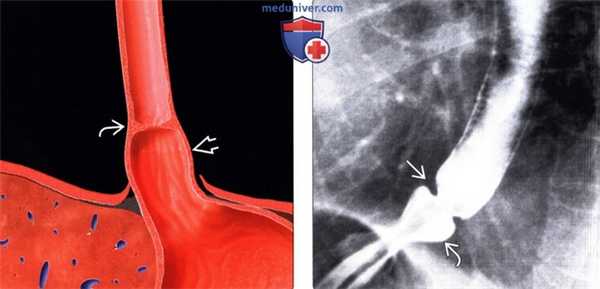

(Слева) На рисунке показана небольшая грыжа пищеводного отверстия диафрагмы и циркулярное сужение просвета пищевода в виде кольца В в области пищеводно-желудочного перехода.

(Справа) На рентгенограмме, полученной во время рентгеноскопии пищевода со взвесью сульфата бария, визуализируется грыжа пищеводного отверстия циафрагмы В небольшого размера и кольцо Шацкого, приводящее к сужению просвета пищевода до 5-7 мм. Симптоматическое сужение просвета за счет кольца Шацкого (в области кольца В), скорее всего, является результатом рефлюкс-эзофагита.

(Справа) На рентгенограмме, полученной во время рентгеноскопии пищевода со взвесью сульфата бария, визуализируется грыжа пищеводного отверстия циафрагмы В небольшого размера и кольцо Шацкого, приводящее к сужению просвета пищевода до 5-7 мм. Симптоматическое сужение просвета за счет кольца Шацкого (в области кольца В), скорее всего, является результатом рефлюкс-эзофагита. (Слева) При рентгеноскопии подростка, предъявляющего жалобы на острую боль в грудной клетке, возникшую после проглатывания куска мяса, определяется кольцо Шацкого, виден дефект наполнения, обусловленный искомым кусочком мяса, находящимся над кольцом.